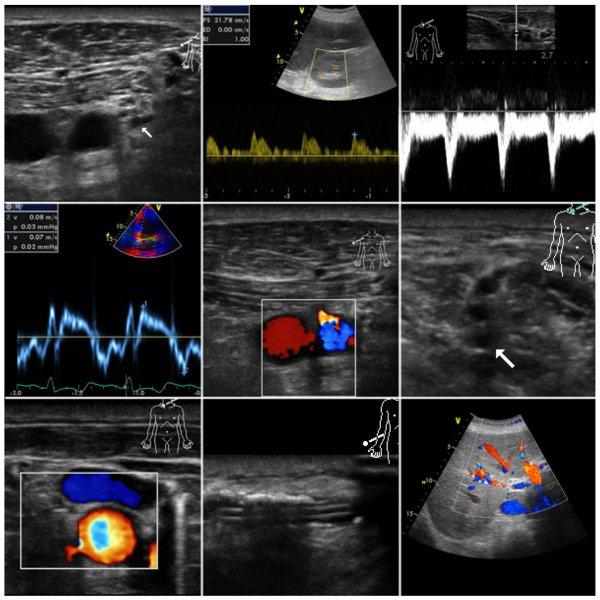

Der Einsatz von Ultraschallgeräten zur Diagnostik sowie Intervention ist mittlerweile aus dem anästhesiologischen und intensivmedizinischen Alltag nicht mehr wegzudenken. So ist es verständlich, dass die Ausbildung in der Ultraschalldiagnostik und der ultraschall-gesteuerten Punktionen für Anästhesistinnen und Anästhesisten eine wachsende Bedeutung einnimmt. Dies spiegelt sich auch in den Fachgesellschaften wieder, die der Ausbildung einen immer höheren Stellenwert beimessen.